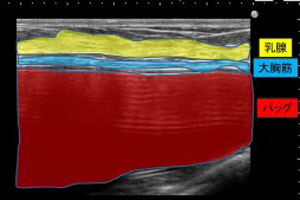

[3]胸内をエコー検査

最後に。バストの中の正確な状態を把握するために、エコー検査は欠かせません。豊胸シリコンバッグが破損していないと思っていた患者さんのケースでも、破損していたり、石灰化や拘縮が思いのほか進行していることもあります。また、表皮から何cm(数mmの場合も)の位置にバッグがあるのかを知ることも重要です。これは、本当に重要な検査なので、大学病院でも用いているような正確なエコーを導入しているクリニックを選びましょう。例えば、エラストグラフィなどを完備していると安心です。